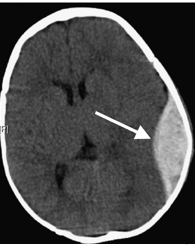

Epidural hematoma

u= an accumulation of blood between the skull and the dural membrane.

uSeen in 2-4% of TBI

uBetween dura and skull

uMost commonly middle meningeal artery

uOverall mortality of 10%

<10% when treated early

Epidural hematoma fun facts

uTypically caused by a focused blow to the head with a blunt object like a baseball, hammer, or baseball bat.

uIn 85-95% of patients, this type of trauma is accompanied by an overlying fracture of the skull.

uBlood vessels in close proximity to the fracture are the sources of the hemorrhage.

uBecause the underlying brain is usually minimally injured, prognosis is excellent if treated quickly and aggressively.

uOutcome from surgical decompression and repair is related directly to patient's preoperative neurologic condition.